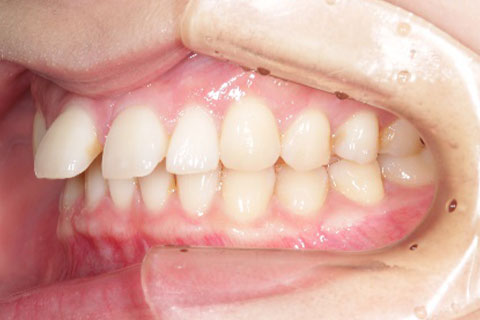

主訴:隙間が気になる

診断名:上顎正中離開

症状:上顎正中離開

患者プロフィール:北九州市・小倉北区30代女性

治療方針:非抜歯矯正治療

治療装置:マウスピース型矯正治療(インビザライン)

抜歯:無し

治療期間:8か月

通院回数:12回

リテーナー: 上顎プレートタイプリテーナー 下顎フィクスタイプリテーナー

治療費用:検査診断料(20,000)+装置料金(500,000)+管理調整料(40,000) +装置撤去時診断料(10,000) +保定装置料金(20,000)=580,000(消費税込)

リスク副作用:痛み・治療後の後戻り・歯根吸収・歯髄壊死

詳しい症例説明: この患者さんは隙間が空いていることを気にされて来院されました。マウスピースタイプの矯正装置で短期間で治療を終えることができました。インビザライン(マウスピース矯正治療)で矯正治療を行うことで治療中も快適に生活できたとのことです。